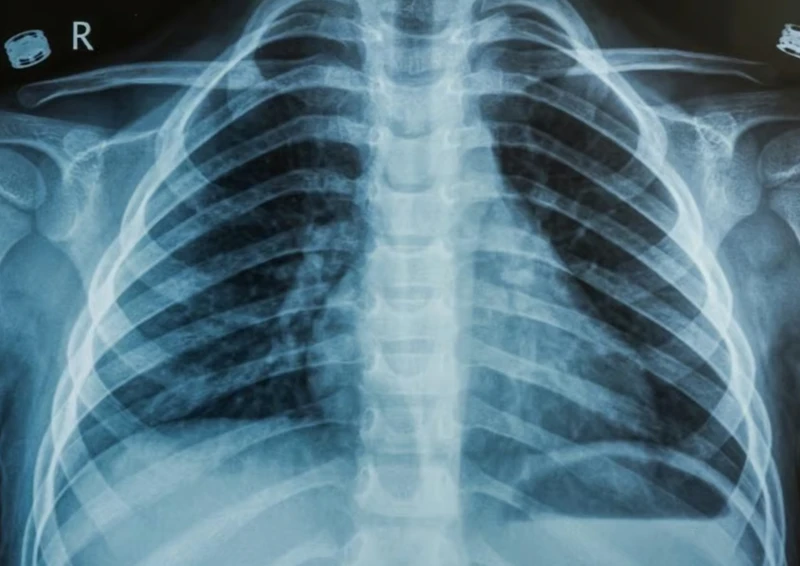

4. Цээжний X-ray-д илрэх өвчинийг Cases дээр тайлбарлах

MNT 30,000.00 or Chest X-Ray